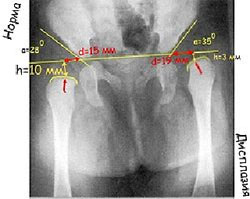

Дисплазия тазобедренного сустава может проявляться не только в виде нарушения вертлужной впадины (ацетабулярная дисплазия), но и в виде неправильного развития проксимального отдела бедренной кости. Форма проксимального отдела бедренной кости чаще всего описывается шеечно-диафизарным углом (ШДУ), который образован срединной линией диафиза и линией, проведенной через центры головки и шейки бедренной кости. Эти измерения проводят на фронтальной рентгенограмме. В зависимости от величины этого угла, в зависимости от того насколько он соответствует возрастной норме, различают нормальную форму проксимального отдела бедренной кости, дисплазию с увеличением этого угла — coxa valga, дисплазию с уменьшением этого угла — coxa vara. Очень важно соотношение между вертлужной впадиной и головкой бедренной кости. Для оценки геометрии тазобедренного сустава применяют много методов, один из них показан на рисунке. Важным показателем является центрация головки бедра и вертлужной впадины. Если провести линию через края вертлужной впадины (АВ) и линию через середину головки и шейки бедра (CF), то линия СF должна проходить через середину (точка О) линии АВ.

Причём угол, образованный этими линиями, должен приближаться к прямому. В этом заключается большой биомеханический смысл: равномерная нагрузка на головку и вертлужную впадину и нормальное развитие этих структур. Угол центрации тесно связан с формой шеечно-диафизарного отдела. В нижней части рисунка показаны некоторые формы дисплазии тазобедренного сустава, связанные с нарушением шеечно-диафизарного угла и угла наклона вертлужной впадины. Рисунок А — норма. Линия наклона вертлужной впадины и срединная линия головки и шейки составляют прямой угол, ШДУ и угол наклона вертлужной впадины не изменены. Рисунок Б — варусная деформация проксимального отдела бедра с нарушением центрации. Рисунок В показывает форму дисплазии с увеличением ШДУ при нормальном угле наклона вертлужной впадины. Рисунок Г — дисплазия, при которой сочетается избыточный ШДУ и избыточный угол наклона вертлужной впадины